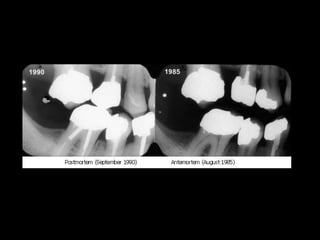

C. COMPARING POST – AND ANTE-MORTEM

DENTAL RECORDS

– Compared by written notes, Study casts, radiographs,

Photographs etc.,

– Criteria for comparison are

a Tooth characteristics [number, eruption status,

position]

b. Personal characteristics

[crown morphology - occlusal ridges, cusps,

Root morphology - branching pattern, furcation,

fusion]

c. Complexity factors – tubercles, pits, additional

ridges, grooves, fissures &

d. Acquired features – hypoplasia, trauma, function,

personal habits, restorations

– Individual with multiple dental treatment & unusual

features – better identified.

– Dental record considered a legal document

– Radiographic identification is often conclusive.